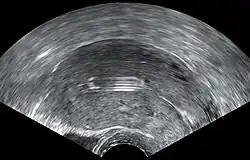

![]() Dispositivo intrauterino (diu) con progestágeno | ||

El diu[1] hormonal con progestágeno es un dispositivo intrauterino que libera la hormona levonorgestrel. Se utiliza para el control de la natalidad, los períodos menstruales abundantes y para prevenir la acumulación excesiva del revestimiento del útero en aquellos que reciben terapia de reemplazo de estrógenos. Es una de las formas más efectivas de anticoncepción con una tasa de fracaso anual de alrededor del 0.2%. El dispositivo se coloca en el útero y dura de tres a cinco años. Después de la eliminación, la fertilidad vuelve rápidamente.